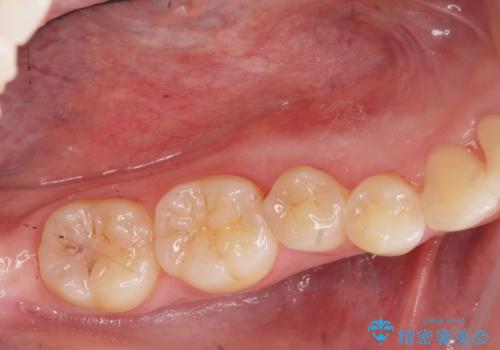

舌のスペースが広くなったと喜んでいただくことができました。

反対側も除去を予定しています。